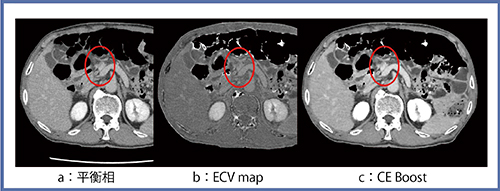

膵頭部管状腺癌では通常,造影CTの動脈優位相で乏血性の領域の描出を期待するが,がんが小さく,ある程度多血性である場合,ほとんど検出できないことがある。そのような症例では,腺癌の線維化を反映した平衡相での濃染を検出することがポイントになる2)。本症例にて通常の平衡相,ECV map,CE Boost画像を比較すると,CE Boost画像が視覚的には最も明瞭であった(図4)。

図4 膵頭部管状腺癌(76歳,男性)